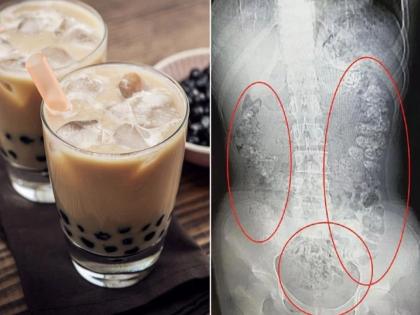

चहाचे तुम्ही वेगवेगळे प्रकार ऐकले असतील. ज्यात ग्रीन टी, ब्लॅक टी आणि हर्बल टी यांचा समावेश आहे. पण तुम्ही कधी बबल टी बाबत ऐकलं आहे का?

चहाचे तुम्ही वेगवेगळे प्रकार ऐकले असतील. ज्यात ग्रीन टी, ब्लॅक टी आणि हर्बल टी यांचा समावेश आहे. पण तुम्ही कधी बबल टी बाबत ऐकलं आहे का? हा एक नव्या प्रकारचा चहा असून याची क्रेझही चांगलीच वाढत आहे. खासकरूण तरूणाईमध्ये हा चहा अधिक लोकप्रिय आहे. पण या चहामुळे एका १४ वर्षीय मुलीला अडचणीत टाकलं आहे.

बबल टी तयार करण्यासाठी त्यात गोलगोल टॅपिओका बॉल्स टाकले जातात. सोबतच त्यात थोडा बर्फ सुद्धा टाकला जातो. त्यामुळे या चहाला बबल टी म्हटलं जातं. दरम्यान, डॉक्टरांनी ऑपरेशन करून मुलीच्या पोटातील बॉल्स काढले. सध्या तिची प्रकती ठिक आहे आणि तिला डॉक्टरांनी बबल टी पासून दूर राहण्याचा सल्ला दिला आहे.